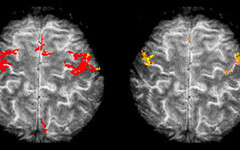

14.01.16 NOORTEADLASED ... Magnetresonantstomograafia uuring võimaldab meil inimkehast teha pildi, kuid see võtab aega ning seda aega tihtilugu pole. Kuidas saada MRT pilt kiiresti ja kvaliteetselt, sellele on võimalik lahendus matemaatikute ja füüsikute kätes.